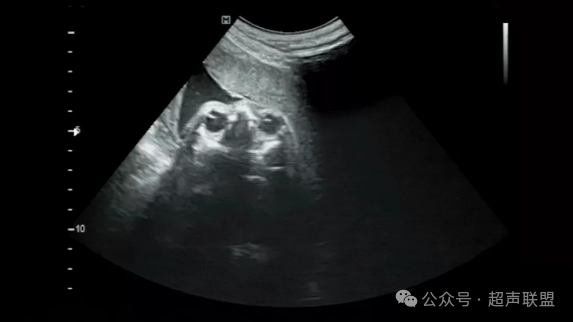

胎头横切面,声束尽量从面部正前方进入,显示两眼眶最大横切面,晶体等大,眼球等大

LD=RD=ID=1/3眼外距

眼眶內距,眼眶外距。眼内距指双侧眼眶内侧壁的距离;眼外距是指双侧眼眶外侧壁的距离。眼距过近或过远均提示胎儿异常。

要求在同一平面内显示双侧晶体及眼球图像,且双侧晶体及眼球大小基本相等。如果显示平面有偏斜,可能会影响到下面各个横切面的正确显示,从而导致假阳性唇裂的诊断。此外,该切面还可显示眼眶骨性高回声、鼻根部骨性高回声及颅内结构。孕周较小的胎儿(30周以内)可显示高回声玻璃体动脉。

1.眼球:双侧眼球及眼球内晶体大小基本相等,晶体内部为无回声。14周后,经阴道超声可显示出眼内的晶体,90%可显示玻璃体动脉。玻璃体动脉一般在30周后消失。玻璃体动脉表现为玻璃体内的细线状高回声,前端与晶状体后壁相连,向后达眼眶底部;

2.眼眶的大小、眼内距及眼外距:眼眶的大小又称眼距是指眼眶的左、右径;眼内距是指双侧眼眶内侧壁的距离;眼外距是指双侧眼眶外侧壁的距离。20周以上胎儿正常时眼内距约等于眼眶左右径(眼距)。如果出现异常或明显不对称或不成比例,则应测量这些数据并查阅生长发育参数表来判断;